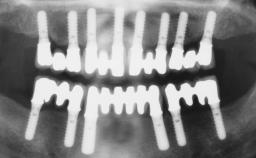

A fully edentulous 65-year-old woman was referred to our clinic for esthetic and functional dental rehabilitation. The patient presented with inadequate complete maxillary and mandibular prostheses, insufficient vertical dimension, and extensive tooth wear. The clinical examination and anamnesis showed no local or systemic contraindications, no signs or symptoms of bruxism, and an absence of smoking habits. The treatment proposed was implant placement in the mandibular interforaminal area and immediate loading with a fixed definitive prosthesis. A removable mucosa-supported complete prosthesis was indicated for the upper jaw, since its bone structure offered satisfactory retention and the financial condition of the patient disfavored a full-mouth implant-supported rehabilitation.

# of Implants 4

Defining Characteristics Fully edentulous lower jaw to be rehabilitated with two or more implants

Modality 3 or 4 interforaminal implants